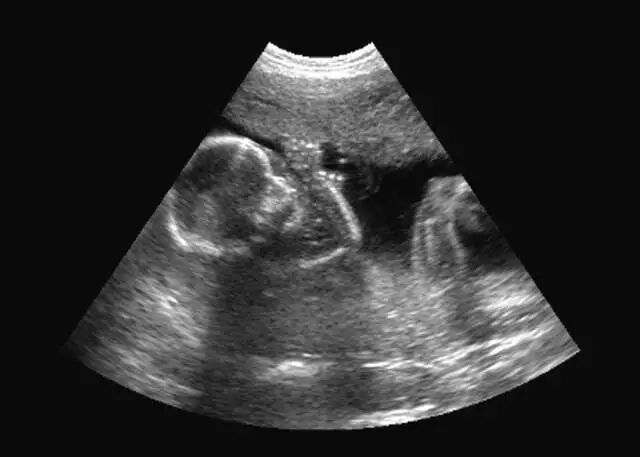

怀孕32+周时做超声检查,发现胎儿腹腔内有一个5cm*6cm大小的肿瘤,这个消息让小钱夫妇满怀期待的心情蒙上了阴影。

接下来,随着胎儿数周胎儿增大,肿瘤也在不断变大。为了寻找解决的办法,夫妇俩打电话四处问人。随着时间的流逝,辗转了数家医院,都是没有结果。

那天,正逢区妇幼保健院产科王莉钦主任的专家门诊,他们找到了王莉钦主任,王主任考虑胎儿已成熟,腹腔囊性肿瘤随时有破裂、蒂扭转、甚至危及胎儿生命的可能,建议小钱住院终止妊娠,并给她安排了第二天进行剖宫产手术。

经检查发现孩子腹腔内的巨大肿瘤竟是卵巢囊肿,医生在腹腔镜下进行了卵巢囊肿切除术,手术顺利,目前宝宝情况稳定。

区妇幼保健院产科王莉钦主任介绍,胎儿卵巢囊肿还是比较少见的,发病原因目前还不明确,最大的可能是由于来自母亲和胎儿的促性腺激素的双重影响,没有遗传倾向,也不是羊水穿刺染色体核型分析检查的适应症。

胎儿出生前卵巢囊肿易发生变化,有些会消失,有些会变成复杂囊肿,有些保持稳定。囊肿会发生囊内出血、破裂出血、卵巢扭转等风险,巨大包块会使胎儿出生后会发生呼吸困难,建议孕妇应到具备小儿外科技术能力的医院进行分娩。